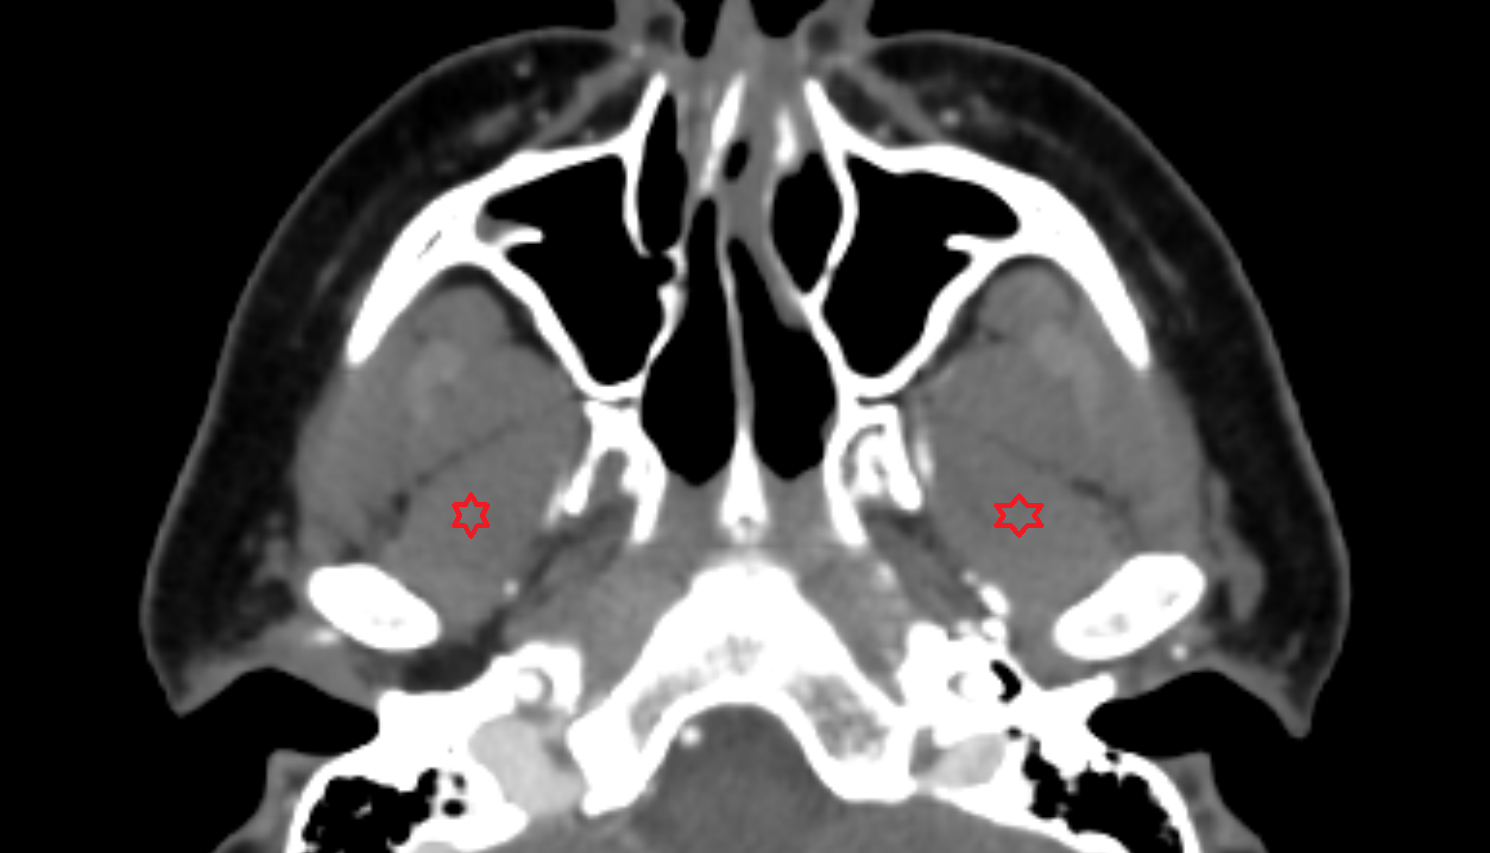

- Maxillary sinus

- Lateral pterygoid muscle

- Medial pterygoid muscle

- Superior head of lateral pterygoid muscle

- Inferior head of lateral pterygoid muscle